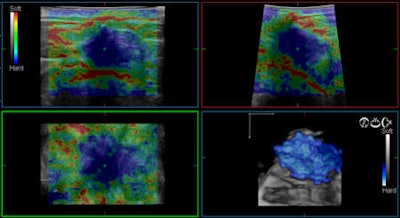

A benefit of using elastography is there is no freehand compression and decompression at the body surface. Moreover, propagation of shear waves happens in 1 to 10 m/sec.

"From my point of view, the shear wave access is the one with the highest level of standardization," Weismann said. "If you compare this with compression and decompression and you study the results afterward, it is always a problem if the individual has a strong influence on the result or outcome. You can reduce this if there is no need to compress or decompress but only to keep the transducer stable in position in the region of interest. This is a very strong point for standardization."

Also, tissue elasticity is directly measured in kPa. Not to mention it is independent of user skill. In the future, analysis of elasticity will be offered by CAD, he pointed out.